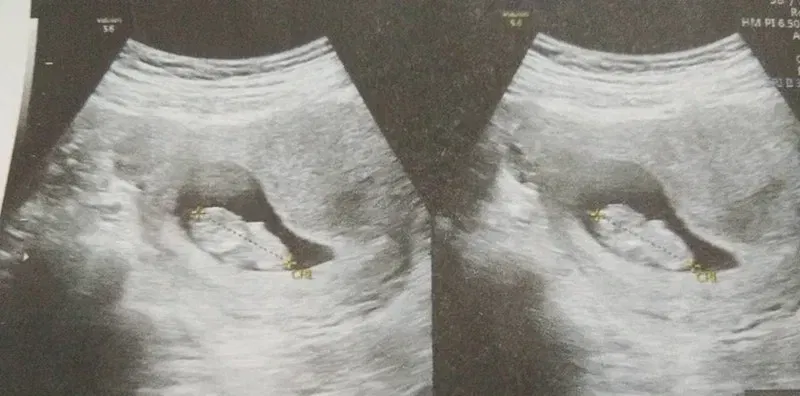

🚫 สัญญาณเริ่มต้นของการแท้งบุตรใน ไตรมาสที่ 2 😱

ระวังและรีบไปพบแพทย์หากคุณมีอาการเหล่านี้ค่ะคุณแม่ อันตรายมาก 👇